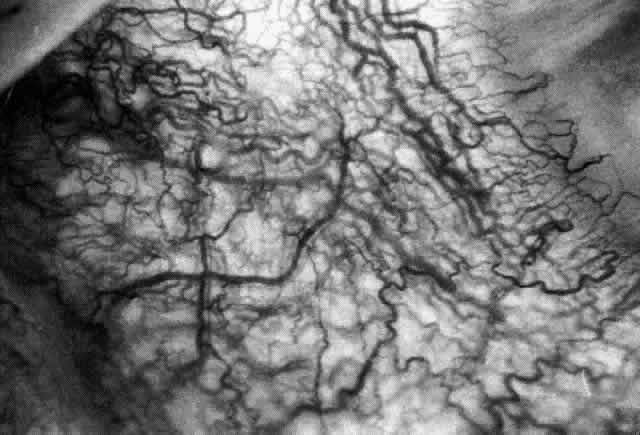

The redness of simple episcleritis may be intense, varying from a fiery-red or a brick-red discoloration to a mild red flush, but it does not have the bluish tinge that is seen in scleritis. The distribution is usually sectorial but can involve the whole anterior segment of the globe. The episcleral vessels are engorged but retain their normal radial position and architecture (Figs. 13 and 14; Color Plate 1A). In simple episcleritis, there is a diffuse edema of the episcleral tissues. These tissues are sometimes infiltrated with gray deposits that appear yellow in red-free light. Surprisingly, the eye is rarely tender to the touch.

Fig. 13. Infiltration of the episclera in which the superficial episcleral vessels show maximal congestion. Conjunctival vessels are slightly congested, as is the deep episcleral plexus, whose irregular criss-cross pattern can be seen deep to the radially arranged superficial episcleral plexus.